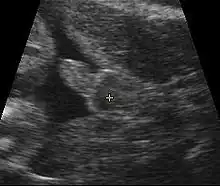

A gestational sac can be reliably seen on transvaginal ultrasound by 5 weeks' gestational age (approximately 3 weeks after ovulation). The embryo should be seen by the time the gestational sac measures 25 mm, about five and a half weeks.[10] The heartbeat is usually seen on transvaginal ultrasound by the time the embryo measures 5 mm, but may not be visible until the embryo reaches 19 mm, around 7 weeks' gestational age.[5][11][12] Coincidentally, most miscarriages also happen by 7 weeks' gestation. The rate of miscarriage, especially threatened miscarriage, drops significantly after normal heartbeat is detected, and after 13 weeks.[13]

Contents in the cavity of the uterus seen at approximately 5 weeks of gestational age

Artificially colored, showing gestational sac, yolk sac and embryo (measuring 3 mm as the distance between the + signs)